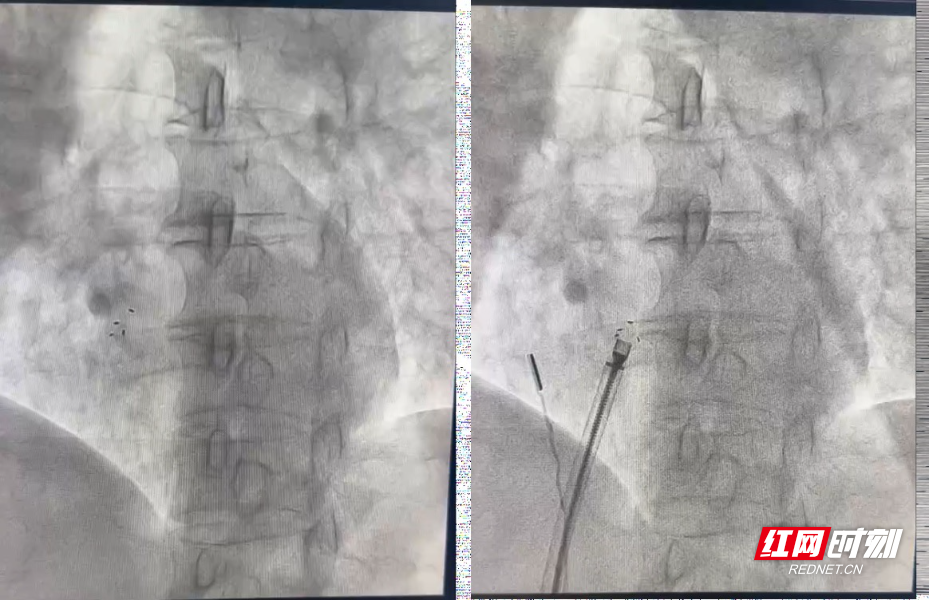

手术过程中,心腔内超声系统宛如医生的“透视眼 ”,清晰呈现出庞女士心脏内部的复杂结构,以及卵圆孔未闭(PFO)与周围组织的解剖关系。石闯团队通过精细操控超声导管,实时调整探查角度与位置,精准引导导丝穿过未闭的卵圆孔进入左心房,成功建立起 封堵操作的通路。这一操作模式,有效避免了传统手术中导丝反复试探可能对心脏组织造成的损伤,同时大幅缩短手术时长,进一步降低了手术风险。

当可降解封堵器的左右盘成功打开后,ICE导管随即对封堵器的位置与封堵效果展开评估。石闯团队通过清晰的实时影像确认:封堵器定位精准、形态稳定,未出现残余分流,且封堵盘与周边组织的贴合关系良好,手术最终圆满成功。术后经密切观察,患者未出现胸闷、胸痛、气促、心悸等不适症状,生命体征保持平稳,符合出院标准,已顺利康复出院。